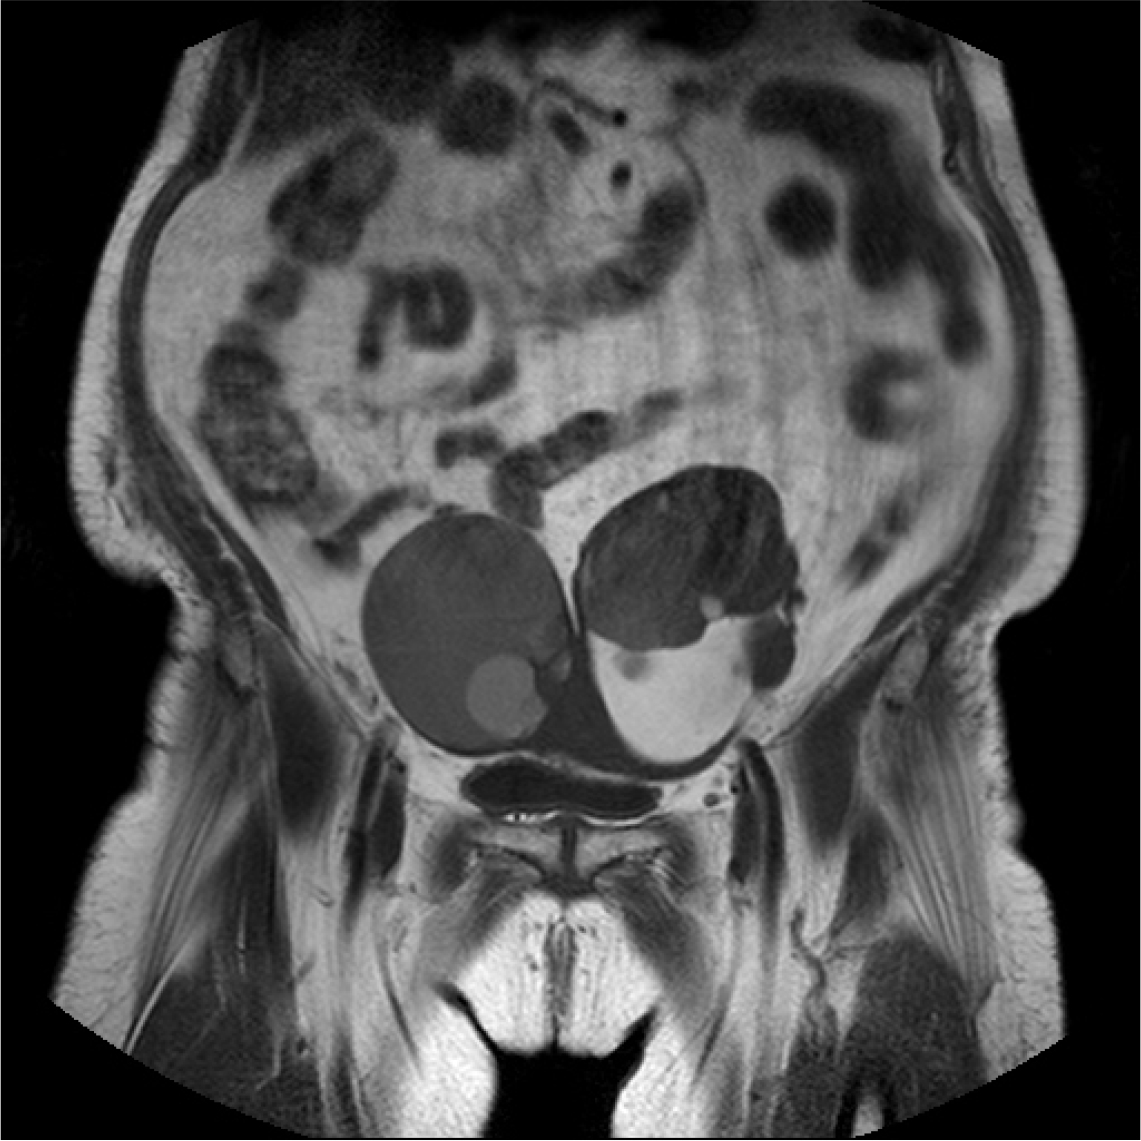

86세의 여성이 배뇨 곤란이 갑자기 심해져서 내원하였다. 환자는 20년 전 요실금 수술을 받은 병력이 있다. 3년 전부터 본원에서 야간뇨와 급박뇨를 치료받던 중 외래 추적 소실 후 3개월 만에 갑자기 발생한 배뇨 곤란 증세로 내원하였다. 신체 검사에서 하복부팽만 및 전신부종소견이 있었다. 초음파검사에서 왼쪽 난소 heterogenous density solid and cystic tumor, 오른쪽 난소에 large cystic tumor 소견이 관찰되었다. 골반 CT를 시행하였고 both ovaries malignancy Krukenberg tumors, 10 cm in each sides secondary stomach tumor 소견이 관찰되었다. 환자는 대학병원으로 전원되었으나 3개월후 사망하였다.

크루켄버그 종양(Krukenberg tumor)은 대개 소화기관에서 기원한 종양이 난소로 전이되는 난소의 전이성 종양으로, 전체 난소 종양의 1∼3%정도를 차지하는 것으로 알려져 있다. 본 케이스는 소화기관, 위암이 난소로 전이된 상태였다. 크루켄버그 종양은 점액 변성과 반지세포(signet ring cell)가 특징적이고 대부분 양쪽 난소 모두 침범된다. 원발암이 진행된 다음에 발견되기 때문에(위암 4기) 크루켄버그 종양이 발견된 지 약 1년 이내에 대부분의 환자가 사망한다. 크루켄버그 종양은 산부인과에서도 희귀한 증례이며, 특히 본 증례는 배뇨증상이 환자의 주 호소 증상이었던 크루켄버그 종양이라는 점에서 의의를 찾을 수 있다.